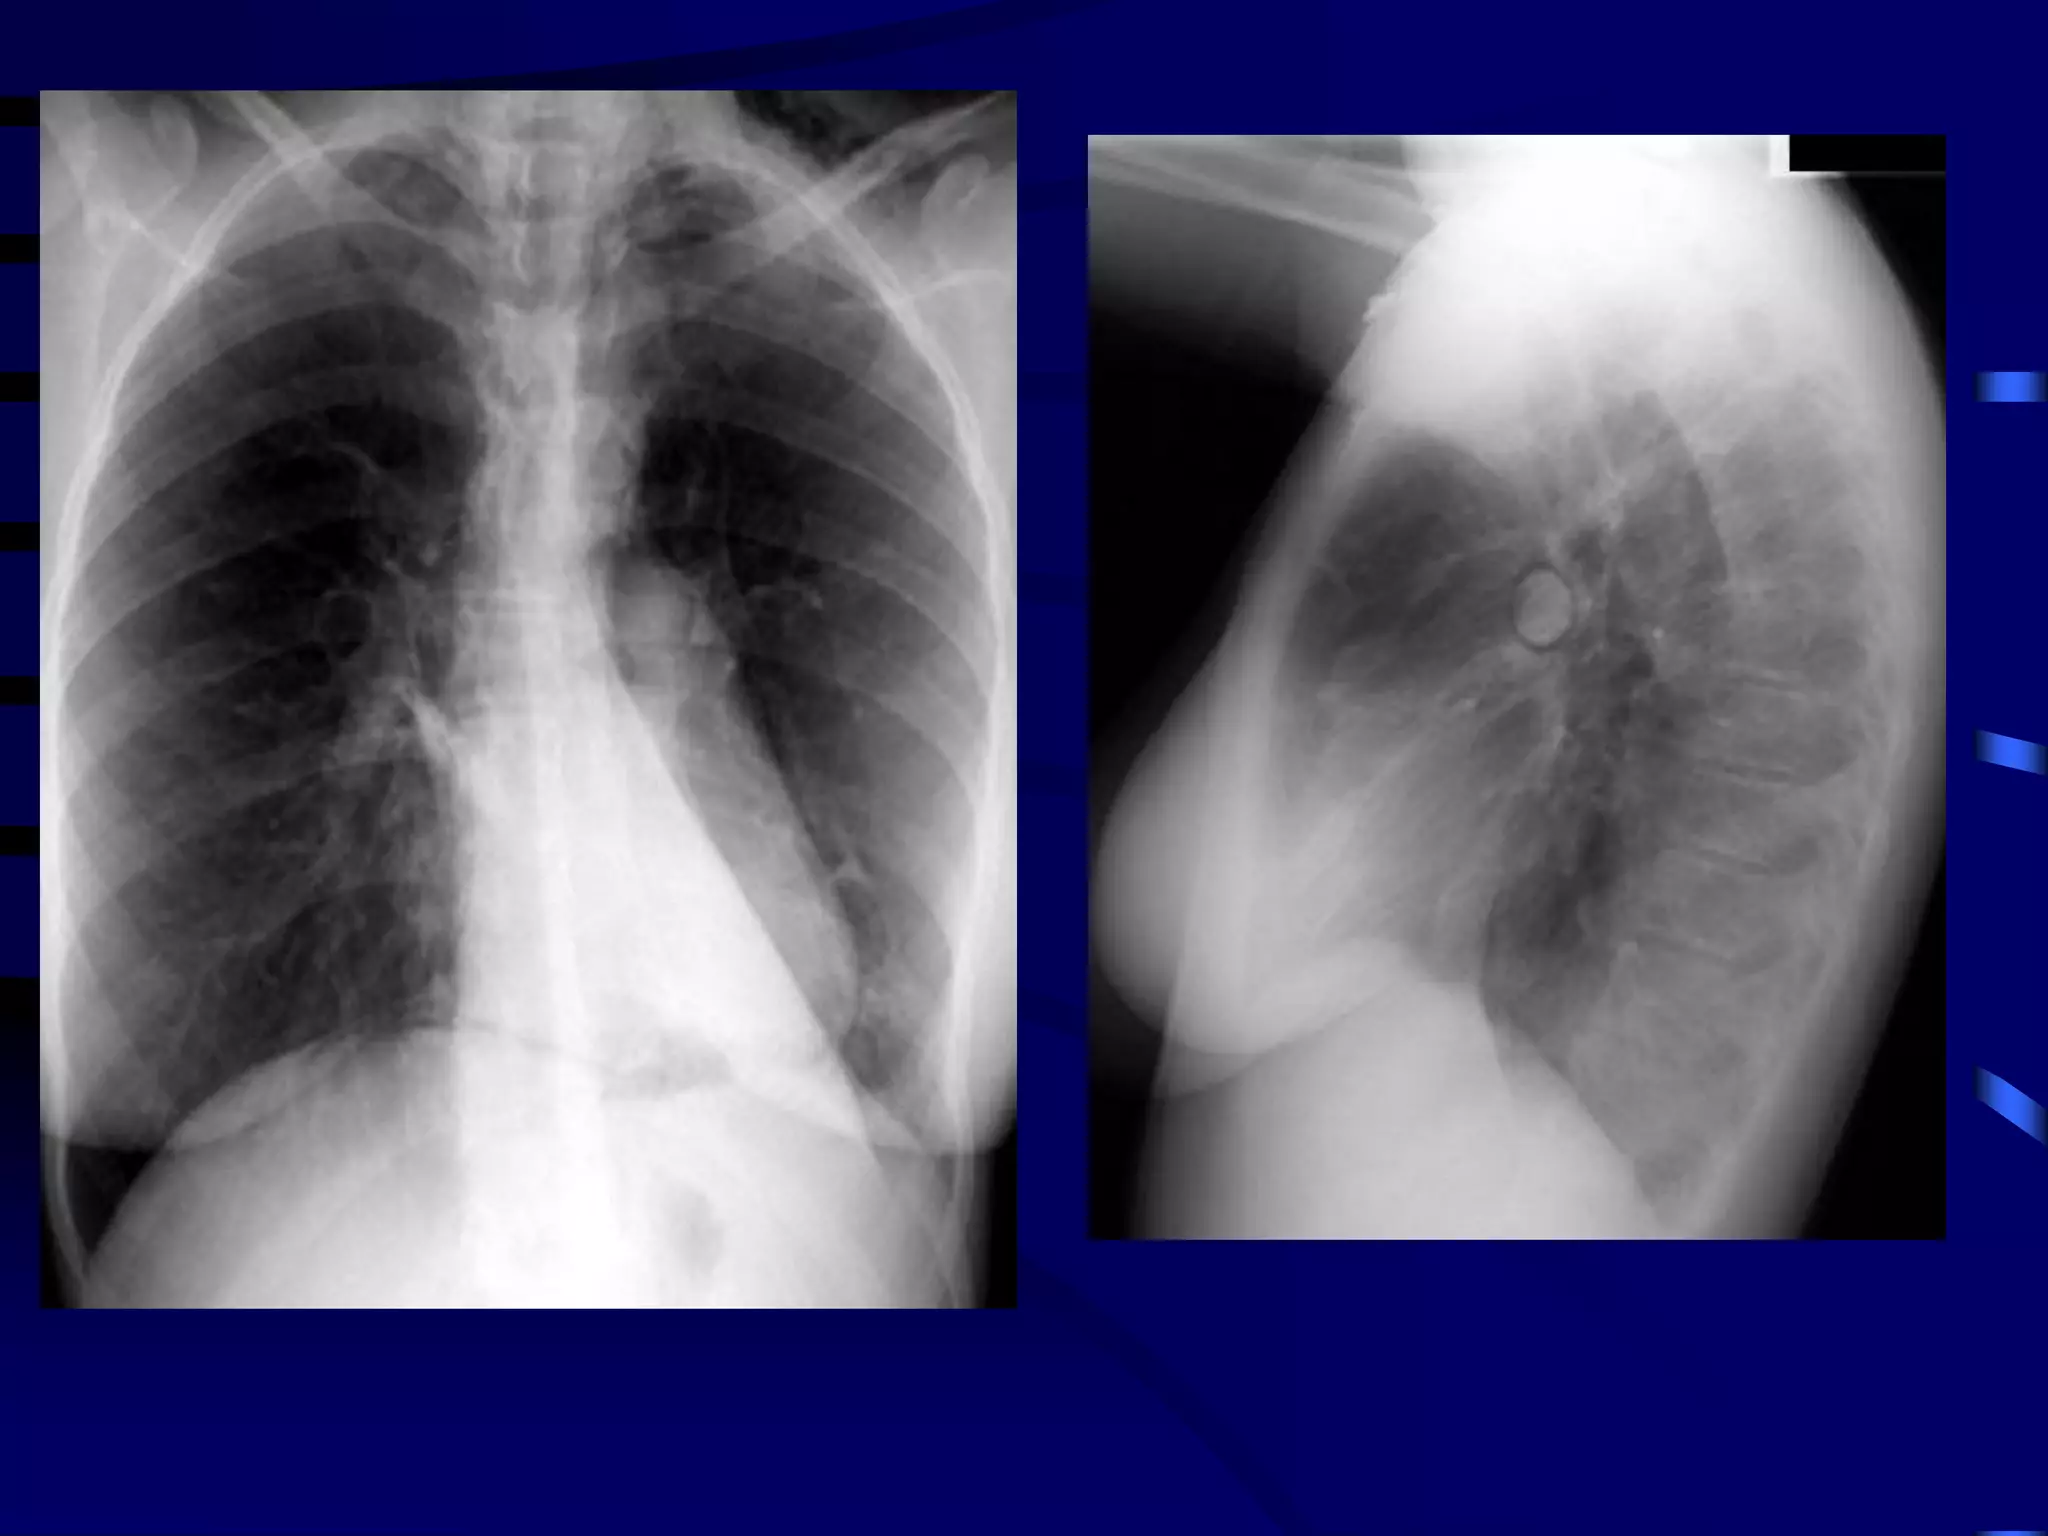

A 46 year old man comes to your clinic for management of

his asthma. He takes high-dose inhaled corticosteroids

and a long-acting beta agonist, along with a leukotriene

inhibitor. His adherence and technique are perfect.

He still has symptoms of cough, wheezing, and chest

tightness that bother him most days and nights each

week. He is using albuterol daily. The symptoms persist

when he goes on vacation out of state.

Sputum culture is negative. IgE level is 3,600 ng/mL. His

primary doctor obtained imaging and a chest CT, which

are shown.

Case 3

Allergic bronchopulmonary aspergillosis (ABPA) is an

ongoing hypersensitivity reaction in response to

bronchial colonization by Aspergillus, and is a common

cause of poorly controlled asthma. Cystic fibrosis

patients are also often affected. Bronchial obstruction

by mucus and chronic inflammation can lead to

bronchiectasis and lung fibrosis with irreversible loss

of lung function.

Clinical features: Cough productive of sputum, frequent

"bronchitis"; often with dyspnea and wheezing.

Lung opacities on chest x-ray or chest HRCT

Central bronchiectasis present on chest CT